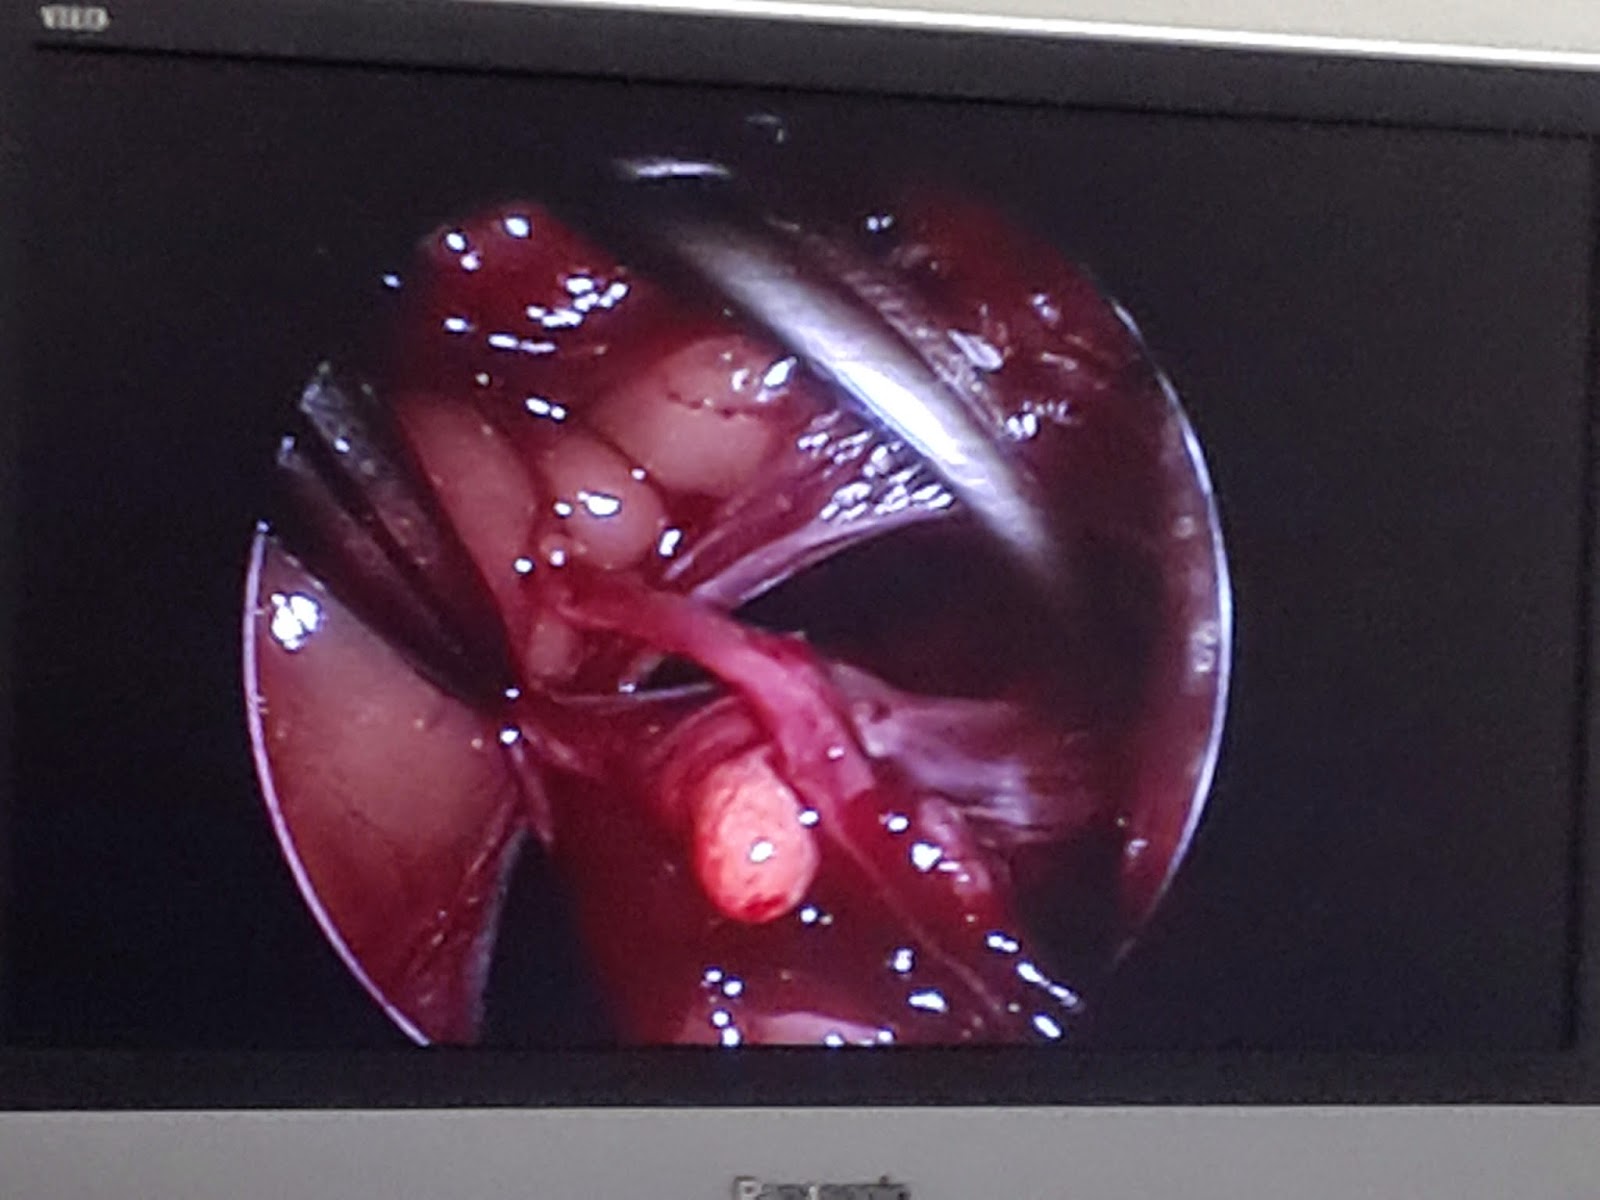

You might be wondering how surgeons get inside the turtle. It turns out that one of the methods is to make an incision in the soft area in front of their back legs (or front, depending on what you want to do). Then they can stick an endoscope in, with a light source and a camera on it, and use tiny instruments with long handles. The best part is that the light makes the internal cavity of the turtle glow, and you can see it through the shell on their belly!

I can't find any good photos on google, so I'm going to show you the ones I took. I'm not sure if we're allowed to do that, so uh, don't tell the school on me please.

The screen showing the instruments and tissues on the endoscope.